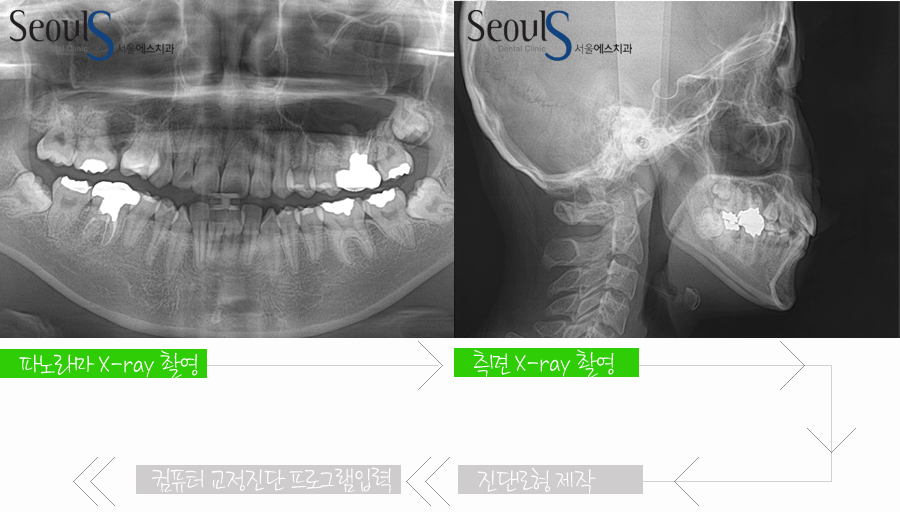

진단은 파노라마 X-RAY 촬영, 측면 X-RAY 촬영, 진단 모형 제작 및 3차원 분석 후

컴퓨터 교정 진단프로그램(V-ceph)에 입력하는 과정을 거치게 되고